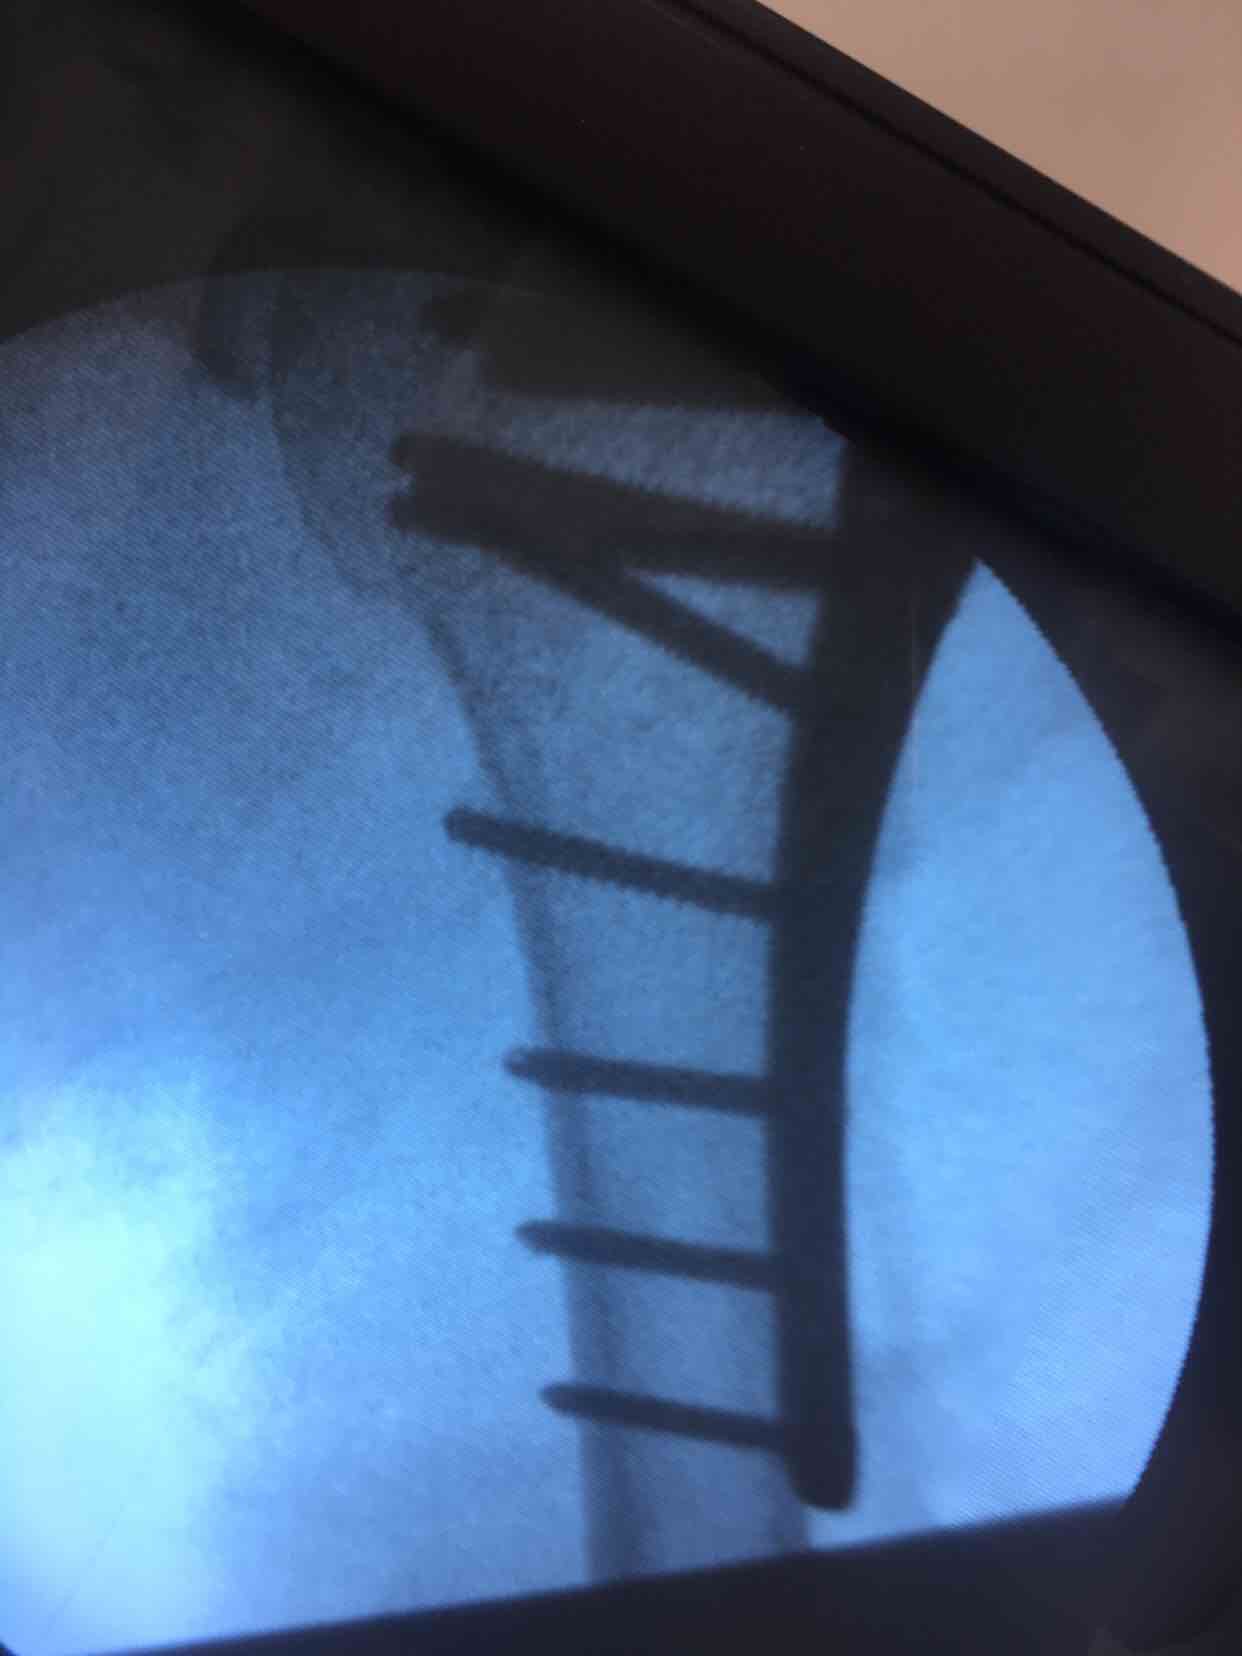

肱骨外科颈粉碎性骨折(切复内固定术)

诊断:肱骨外科颈粉碎性骨折(右)完善术前准备,在臂丛麻醉下行切复内固定术,选肱骨近端锁定钛板,保持稳定性及早期功能锻炼。术后抗炎,消肿等处理。

手术最大优势尽可能解剖复位,保障骨折稳定,早期功能锻炼,避免肩肘腕综合征,骨折移位风险发生。